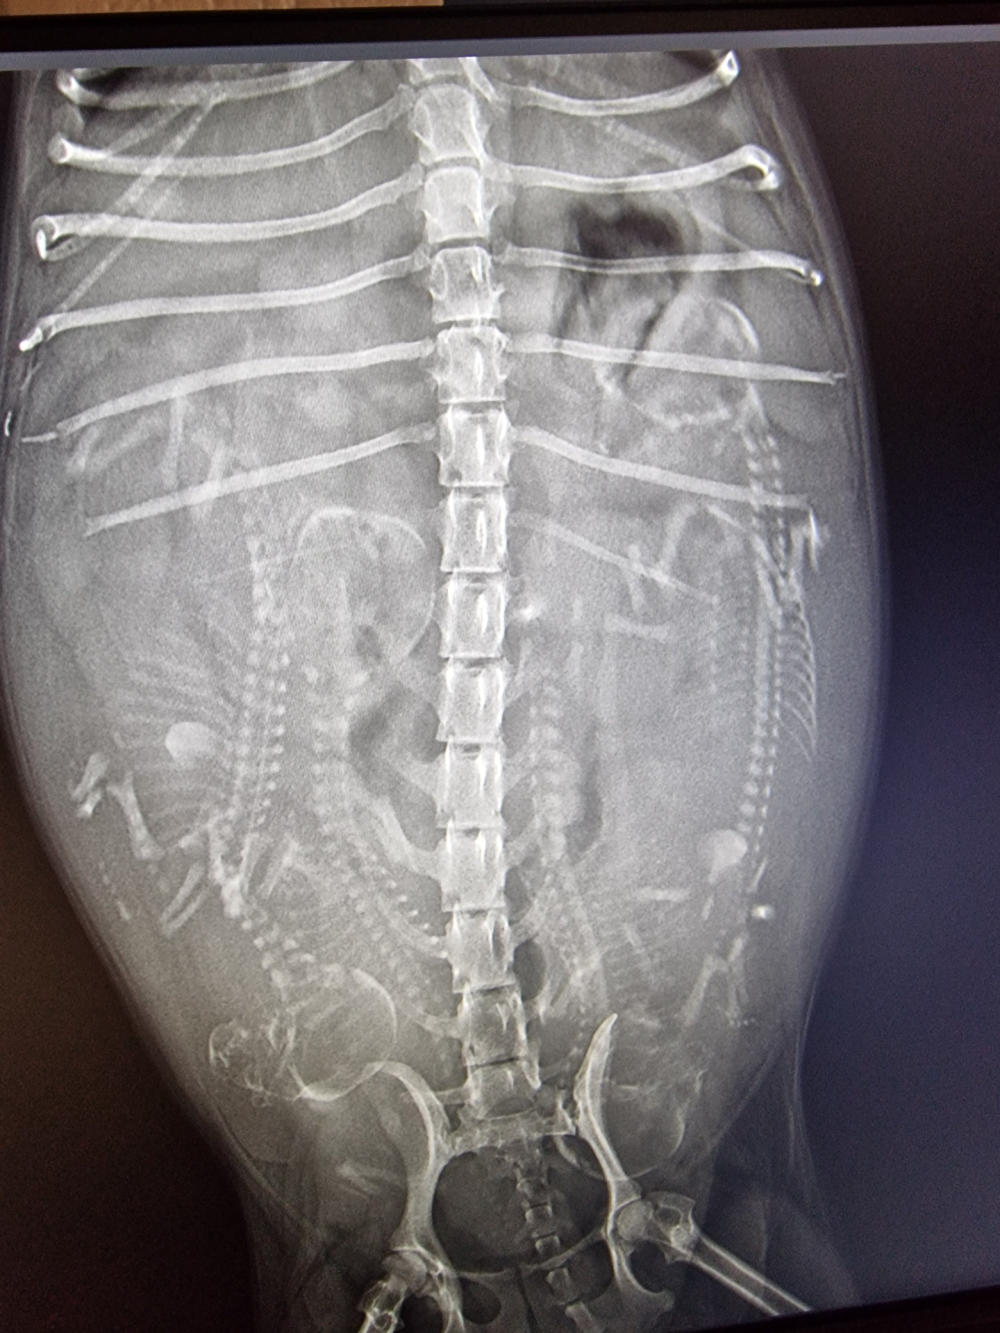

So, heute Morgen war unser Frauli auch mit den anderen drei Mädels zum Röntgen. Im Laufe der nächsten Woche kommt richtig Leben in unsere Bude. Hi, hi. (Röntgenbilder Yule, Lotta und Gina v.l.n.r.) Yule´s Welpen-Nestchen steht auch. Die von Lotta und Gina bauen unsere Niefi´s am Wochenende auf.